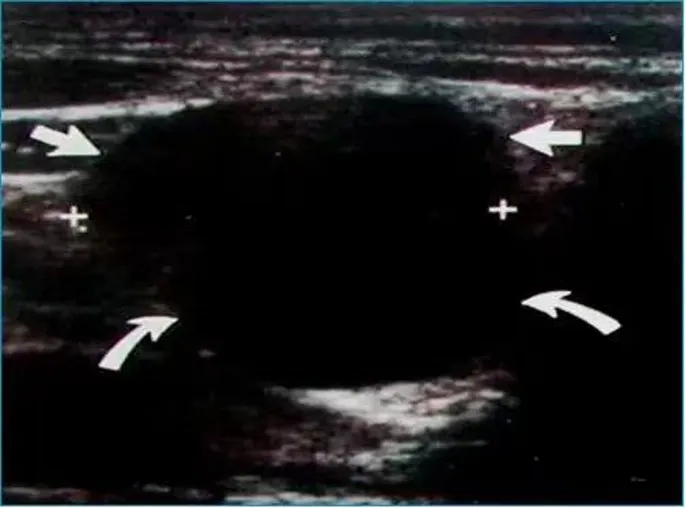

淋巴结转移癌

● 淋巴结不同程度肿大,多呈椭圆形,近圆形,纵横比<2。

● 被膜圆滑或局部隆起,边界清晰或不清晰,淋巴结之间可融合。

● 皮质弥漫性增厚或局限性增厚,内部回声因原发癌不同而异,大多数呈不均匀低-等回声,可有点状钙化或液化。

● 髓质偏心变形或消失。

● 结内血流有多血供、少血供,结内血管失去正常形态,也可为无血供、周边血供。

● 频谱多普勒多显示高速高阻型血流,通常RI>0.7。

肺癌左锁骨上淋巴结转移。

前列腺癌左锁骨上淋巴结转移。

黑色素瘤腹股沟转移。